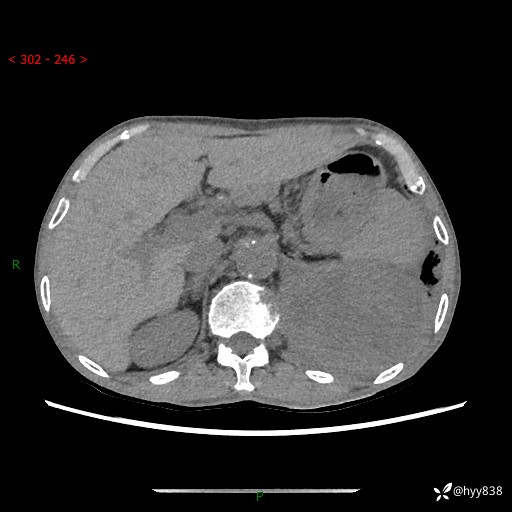

77岁/男,腹痛2月,CT发现左肺占位1天。巨大肿块,肺内或肺外来源…结果公布~

主诉:腹痛2月,CT发现左肺占位1天

现病史:患者于2025年9月间断左下腹胀痛,在当地镇卫生院行彩超检查考虑泌尿系结石,行止痛排石对症治疗未见明显好转;1天前腹痛症状加重,至当地市第三人民医院行CT检查:左肺下叶巨大团块状软组织影,考虑肿瘤性病变,建议增强CT检查;左侧胸腔积液;纵膈内淋巴结肿大;双肺肺气肿;右肺中叶纤维灶。为进一步求治,来我院就诊。

胸部CT平扫+增强